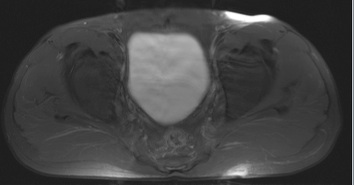

Figure 2 for case Hidradenitis suppurativa

Figure 2